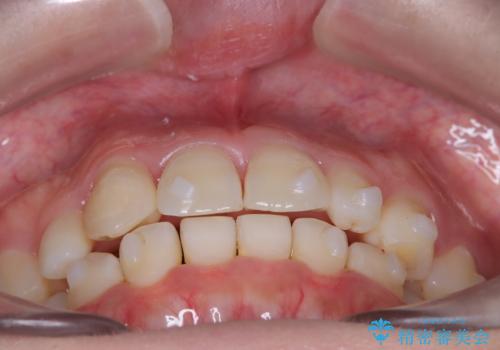

【インビザライン】八重歯が気になる

- 乳歯を抜歯してスペースを確保し八重歯の改善を行いました。

インビザラインをしっかり使用していただいたので、きれいな歯並びになりました。